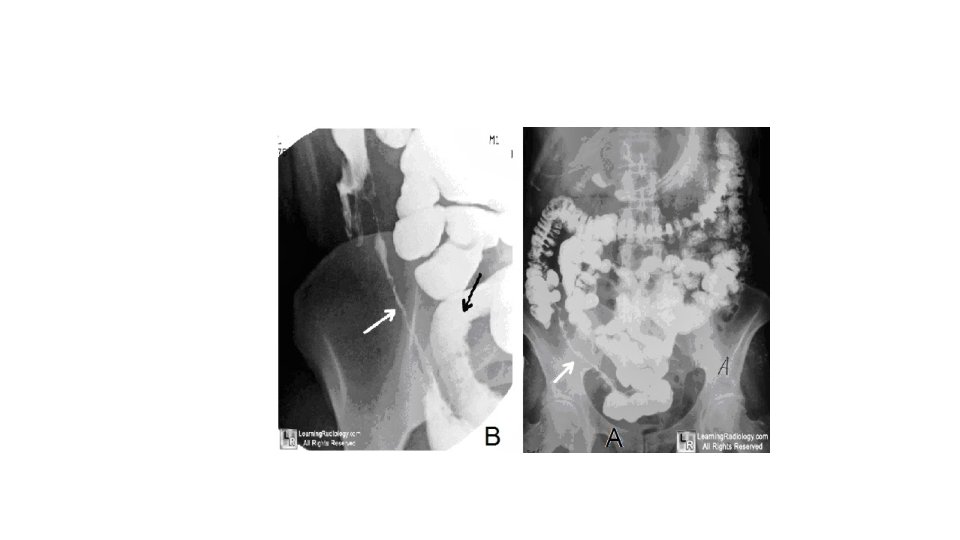

Anal disease In the presence of active disease, the perianal skin appears bluish. Superficial ulcers with undermined edges are relatively painless and can heal with bridging of epithelium. Deep cavitating ulcers are usually found in the upper anal canal; they can be painful and cause perianal abscesses and fistulae, discharging around the anus and sometimes forwards into the genitalia. The most distressing feature of anal disease is sepsis from secondary abscesses and perianal fistulae. Remarkably, the rectal mucosa is often spared and may feel normal on rectal examination. If it is involved, however, it will feel thickened, nodular and irregular. Investigation Laboratory A full blood count needs to be performed to exclude anaemia. There is usually a fall in albumin, magnesium, zinc and selenium, especially in active disease. Protein levels that correspond to disease activity include C-reactive protein and orosomucoid. Endoscopy Sigmoidoscopic examination may be normal or show minimal involvement. However, ulceration in the anal canal will be readily seen. Upper gastrointestinal symptoms may have to be investigated by way of upper gastrointestinal endoscopy, which may reveal deep longitudinal ulcers and cobblestone mucosa. Capsule endoscopy may also have a useful role in those with chronic gastrointestinal bleeding. Imaging Barium enema will show similar features to those of colonoscopy in the colon. The best investigation of the small intestine is small bowel enema. This will show up areas of delay and dilatation. The involved areas tend to be narrowed, irregular and, sometimes, when a length of terminal ileum is involved, there may be the string sign of Kantor. Sinograms are useful in patients with enterocutaneous fistulae. CT scans are used in patients with fistulae and those with intra-abdominal abscesses and complex involvement. Magnetic resonance imaging (MRI) has been shown to be useful in assessing perianal disease. Treatment Medical therapy Steroids are the mainstay of treatment. These are effective in inducing remission in moderate to severe disease in 70– 80% of cases. Steroids can also be used as topical agents in the rectum with reduced systemic bioavailability, but long-term use causes adrenal suppression. They are better at inducing remission than mesalamine but has no role in maintenance. Antibiotics Those who have symptoms and signs of a mass or an abscess are also treated with antibiotics. Metronidazole is used, especially in perianal disease. Its mechanism is unknown and is thought to play a role in suppressing cell-mediated immunity. In a randomised controlled trial, it reduced disease activity in ileocolonic and colonic disease, but not small bowel disease.